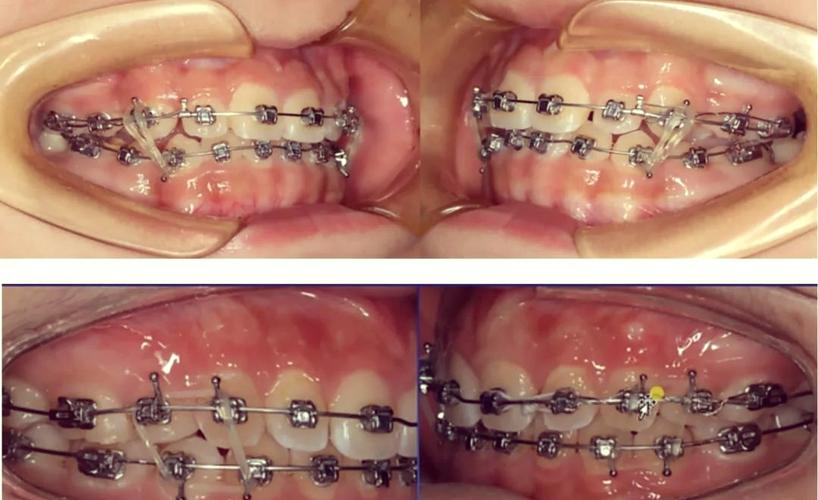

传统固定矫治器是牙齿牵引的经典方法,通过将托槽粘接在牙齿表面,配合弓丝、结扎丝、牵引钩等附件,施加力量移动牙齿,常见类型包括方丝弓矫治器、直丝弓矫治器等,适用于各类错颌畸形,如牙列拥挤、深覆合、深覆盖、反颌等。

- 牵引装置附加:在托槽或磨牙带环上焊接牵引钩,通过橡皮链、螺旋弹簧或弹力线连接需要移动的牙齿与支抗牙,实现“拉”或“推”的效果(如关闭间隙、内收前牙)。

- 定期调整加力:每4-6周复诊一次,更换牵引橡皮链、调整弓丝形态或更换更粗的弓丝,维持牵引力的持续作用。